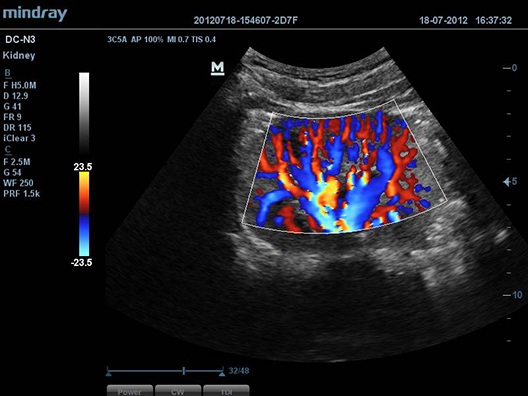

iBeamTM

–ü–æ–∑–≤–æ–ª—è–µ—Ç –∏—Å–ø–æ–ª—å–∑–æ–≤–∞—Ç—å –Ω–µ—Å–∫–æ–ª—å–∫–æ —É–≥–ª–æ–≤ —Å–∫–∞–Ω–∏—Ä–æ–≤–∞–Ω–∏—è –¥–ª—è —Ñ–æ—Ä–º–∏—Ä–æ–≤–∞–Ω–∏—è –µ–¥–∏–Ω–æ–≥–æ –∏–∑–æ–±—Ä–∞–∂–µ–Ω–∏—è, —á—Ç–æ –ø—Ä–∏–≤–æ–¥–∏—Ç –∫ —É–≤–µ–ª–∏—á–µ–Ω–∏—é –∫–æ–Ω—Ç—Ä–∞—Å—Ç–Ω–æ–≥–æ —Ä–∞–∑—Ä–µ—à–µ–Ω–∏—è –∏ —É–ª—É—á—à–µ–Ω–∏—é –≤–∏–∑—É–∞–ª–∏–∑–∞—Ü–∏–∏.